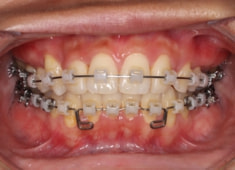

症例紹介

左上3番埋伏歯

治療法:フルパッシブブラケット:T21

治療開始から24ヶ月後